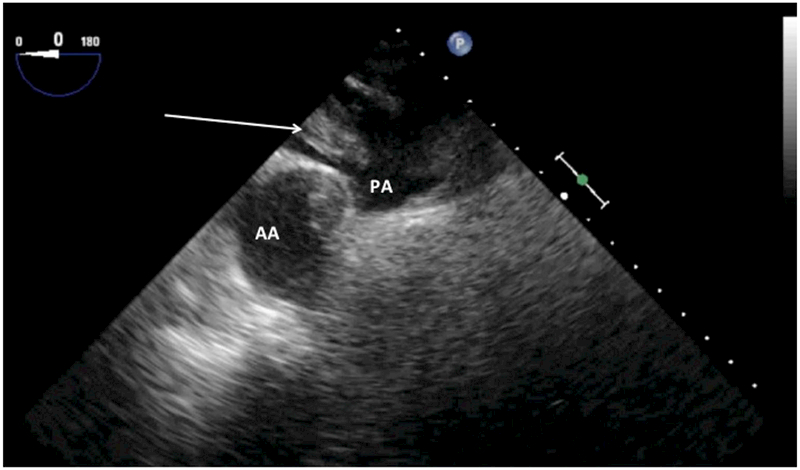

Acute RV failure may raise the suspicion of pulmonary embolism (PE). The proximal pulmonary artery can be visualized for the presence of a thromboembolus (Fig. 3). The development of acute pulmonary hypertension (from both PE and other pathologies) from a sudden increase in the pulmonary vascular resistance may lead to RV failure. The systolic pulmonary arterial pressure or RV systolic pressure can be estimated through Doppler measurement of the tricuspid regurgitation and the right atrial pressure.39 The latter can be estimated from inferior vena cava (IVC) size and change in diameter associated with respiration.38,40 The IVC can be imaged in the transgastric view at the level of the mitral valve (MV) by turning the probe clockwise (to the right) to find the liver. Slight probe withdrawal and transducer angle rotation (30–50°) may be required to optimize the view. M-mode imaging is recommended to measure the IVC size and changes in diameter. In spontaneously breathing patients, IVC diameter is measured and collapsibility (due to a decrease in intrathoracic pressure during inspiration) is assessed. In patients whose lungs are mechanically ventilated, however, distensibility (in response to the increase in intrathoracic pressure during ventilation) rather than collapsibility is assessed.41,42 Patients with an IVC diameter > 2.0 cm with no or minimal respiratory variations (< 50% collapsibility or distensibility) are deemed to have elevated right atrial pressure (>15 mmHg).38

Fig. 3.

Mid-esophageal ascending aorta transesophageal echocardiographic view shows pulmonary embolism in the right pulmonary artery (arrow). AA = ascending aorta; PA = pulmonary artery